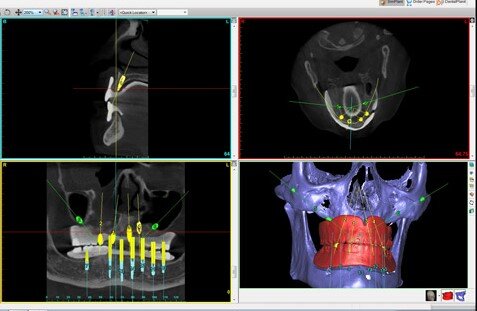

Estudio 3D de la boca del paciente

Gracias a la ayuda de un escáner intraoral de última generación, se obtienen imágenes tridimensionales de la boca del paciente. Con estas y, mediante el uso de un software CAD/CAM, el implantólogo realiza el estudio del hueso maxilar, que servirá para valorar cuál es el lugar más apropiado para colocar el implante y optimizar la cantidad de tejido óseo disponible.

El mismo software del ordenador se emplea para la fabricación de una férula quirúrgica que hará de guía para insertar los implantes en la ubicación y la posición que previamente se ha planificado mediante el ordenador y con la ayuda del TAC 3D.